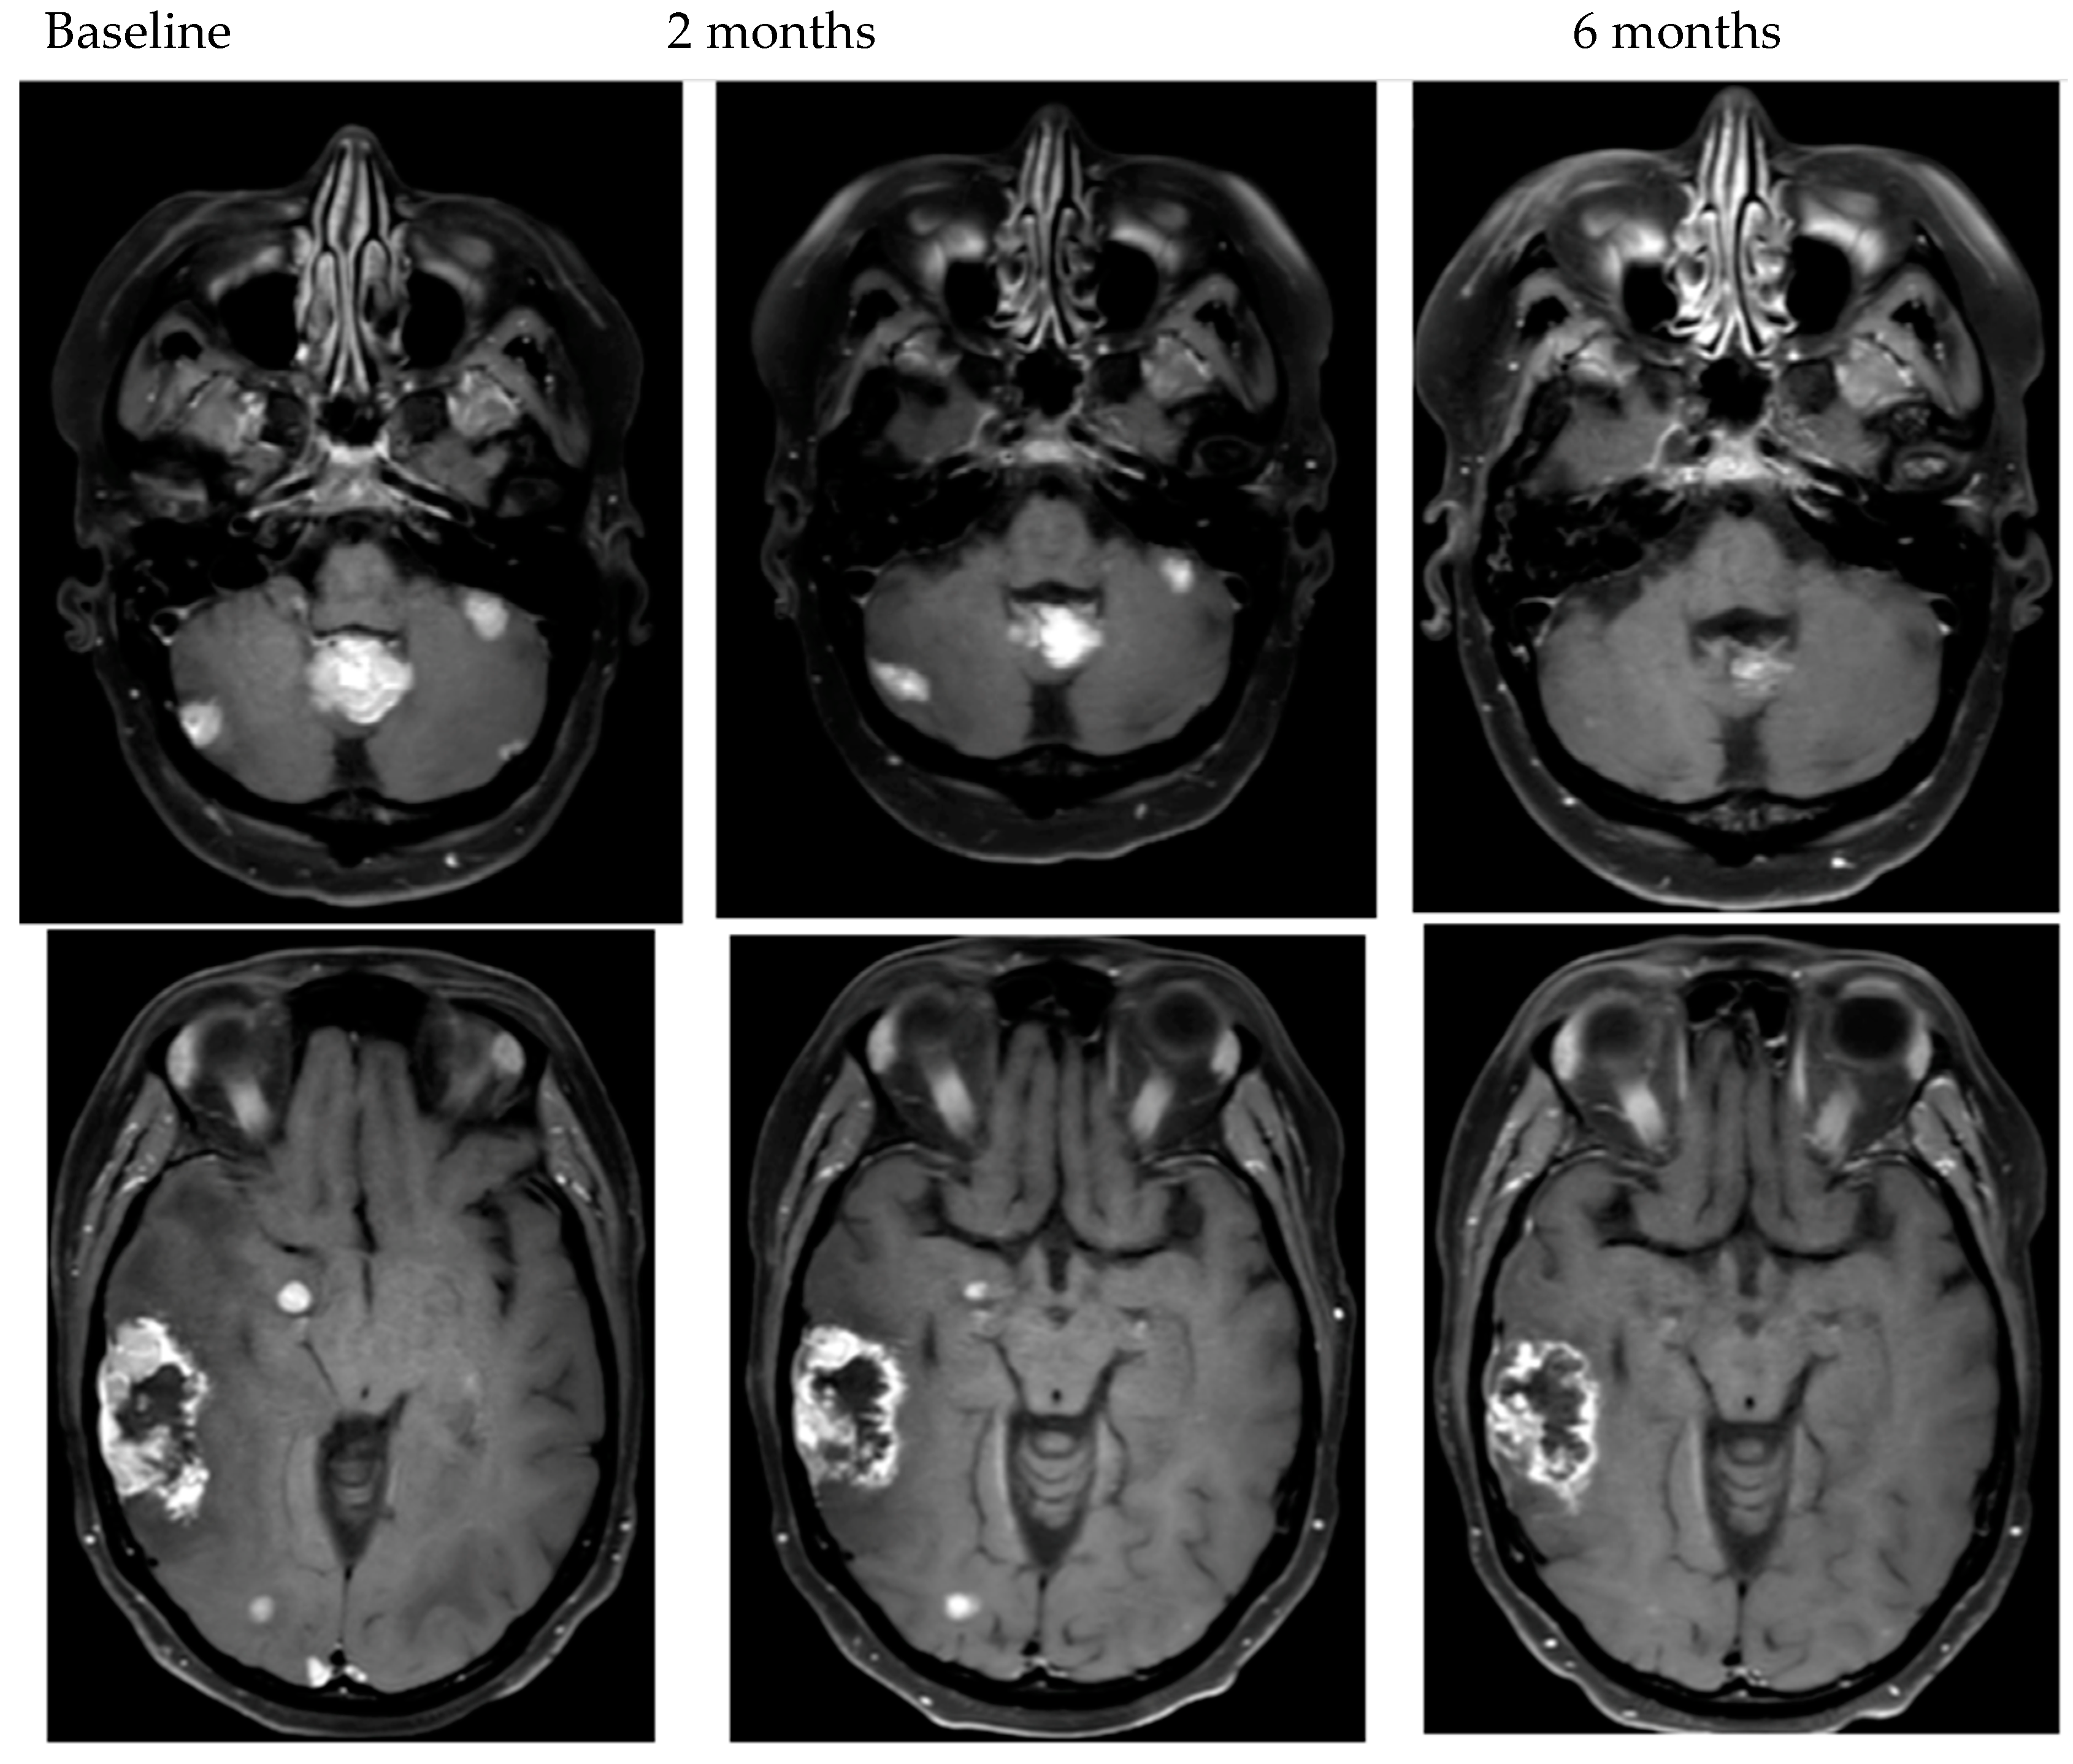

- Bartsch, R.; Berghoff, A.S.; Furtner, J.; Marhold, M.; Bergen, E.S.; Roider-Schur, S.; Starzer, A.M.; Forstner, H.; Rottenmanner, B.; Dieckmann, K.; et al. Trastuzumab deruxtecan in HER2-positive breast cancer with brain metastases: A single-arm, phase 2 trial. Nat. Med. 2022, 28, 1840–1847. [Google Scholar] [CrossRef] [PubMed]

- Pérez-García, J.M.; Batista, M.V.; Cortez, P.; Ruiz-Borrego, M.; Cejalvo, J.M.; de la Haba-Rodriguez, J.; Garrigós, L.; Racca, F.; Servitja, S.; Blanch, S.; et al. Trastuzumab deruxtecan in patients with central nervous system involvement from HER2-positive breast cancer: The DEBBRAH trial. Neuro-Oncology 2022. [Google Scholar] [CrossRef] [PubMed]